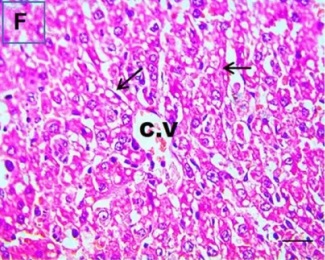

Put the liver tissue section under a microscope, and you can see that cisplatin can cause liver congestion (the blood that should return to the heart is blocked and stagnates in the hepatic veins), cell degeneration (vacuoles appear, which is the earliest change in cellular injury), apoptosis and necrosis, but these conditions can also be alleviated by using Ganoderma lucidum.

Figure 2 Effects of cisplatin and Ganoderma lucidum on hepatocytes